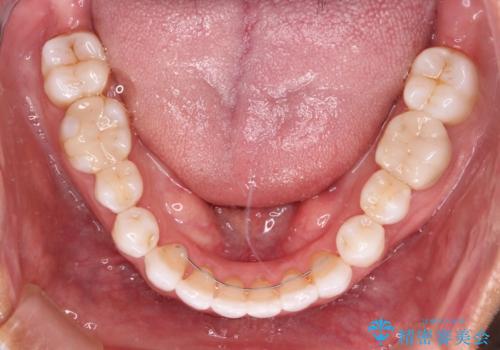

- 治療途中の前歯と上下前歯のデコボコ気にして来院された患者様です。

前歯のデコボコはインビザラインにより歯列を整え、その後に、前歯などをオーダーメイドタイプのオールセラミッククラウンにて補綴治療することとしました。

長時間のマウスピース装着に協力いただき、短期間で歯列をしっかりと改善することができました。

ホームホワイトニングを併用していただいたので、とても明るい口元に仕上がり、患者様には大変満足していただきました。